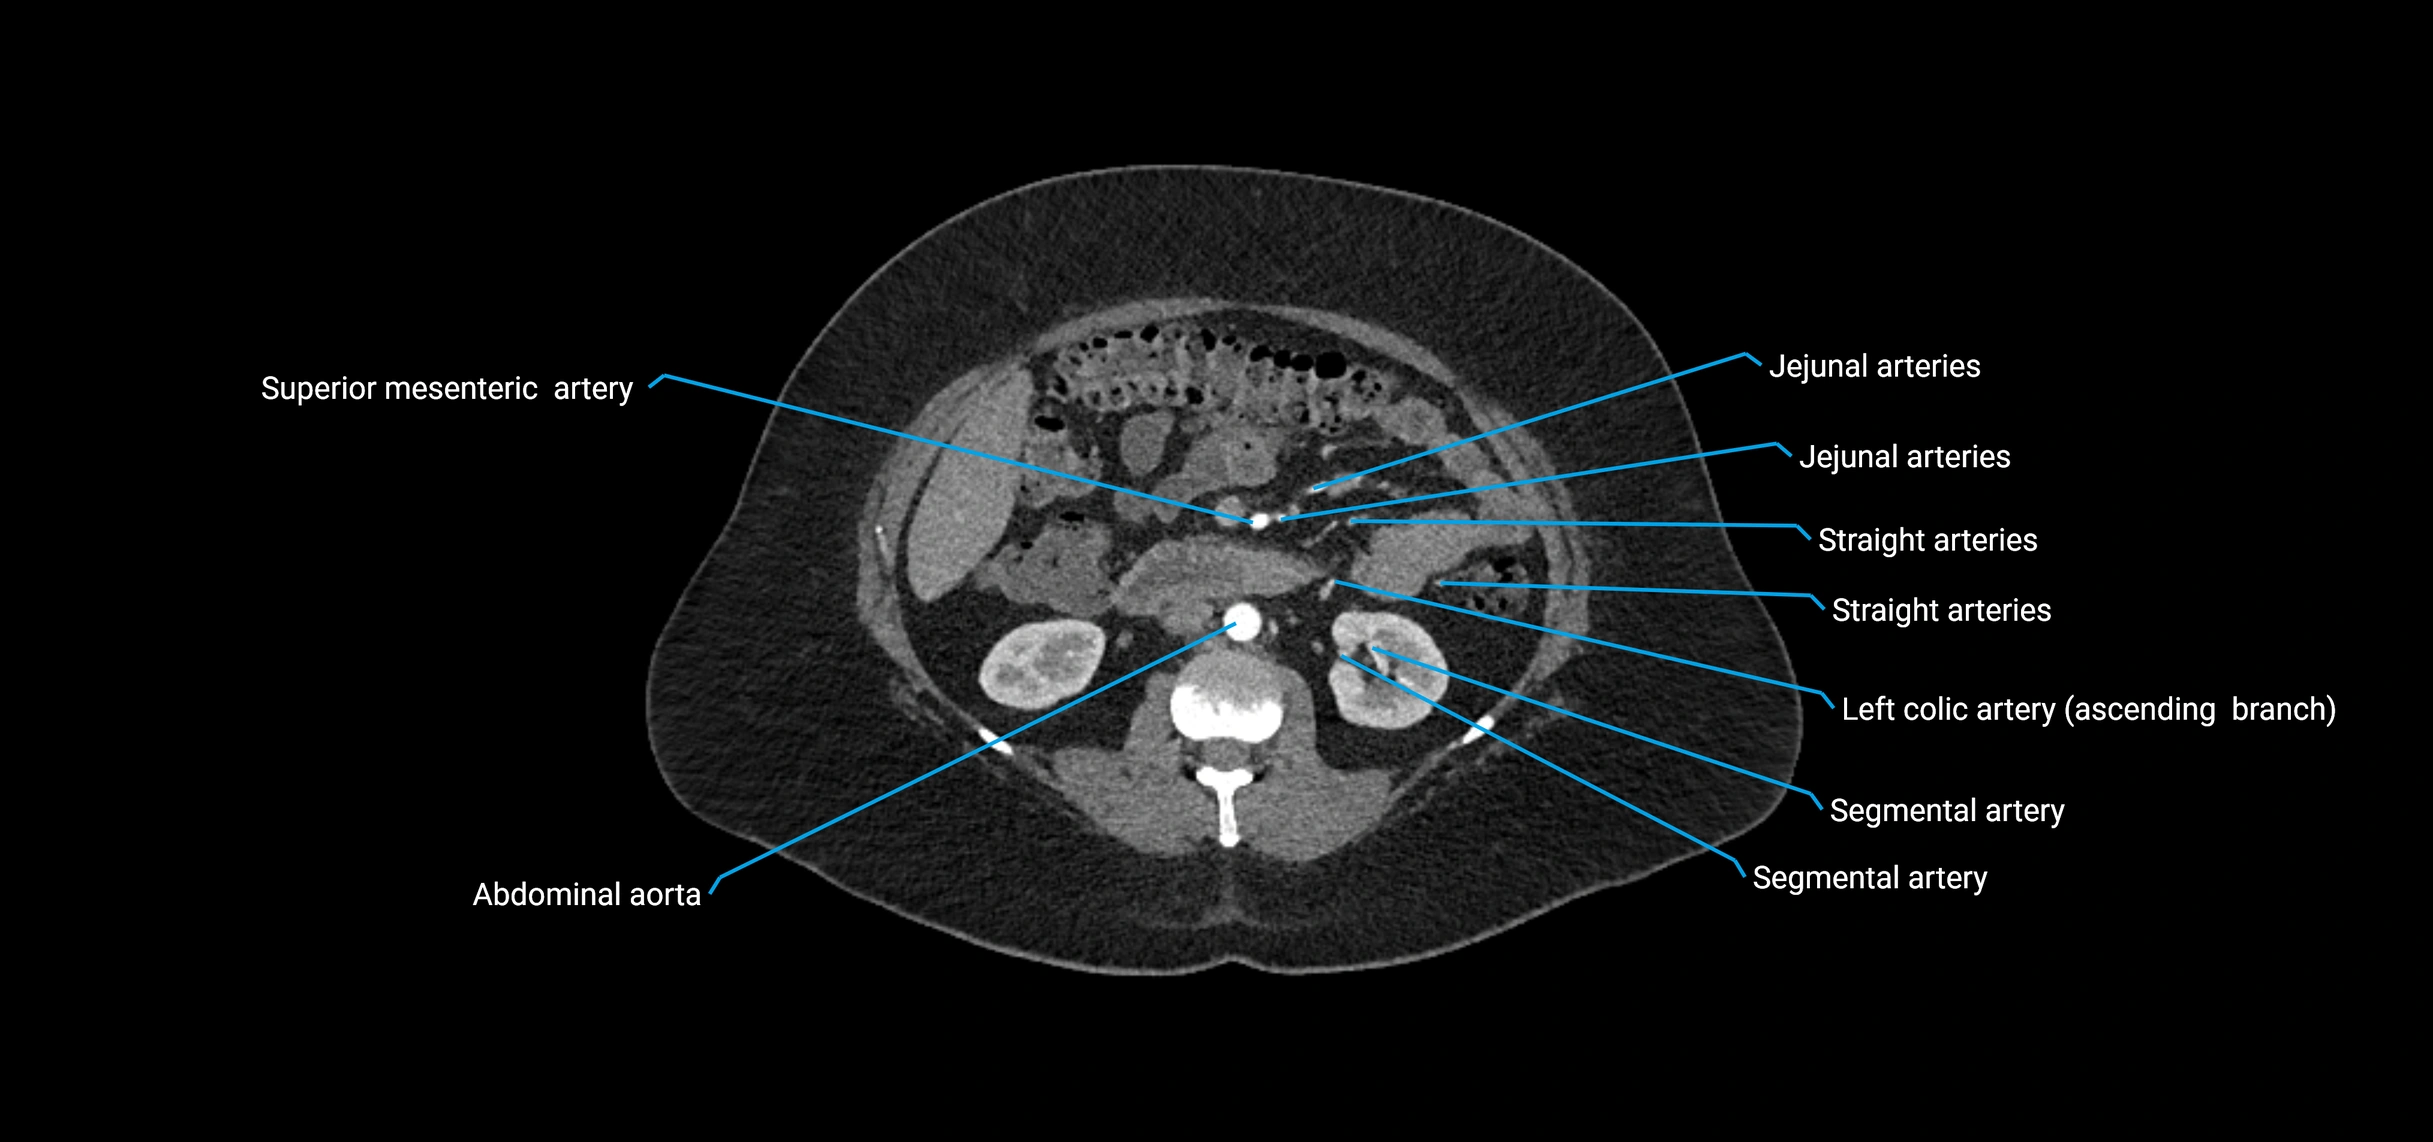

Contrast-enhanced CT (CTA):

• Gold standard for abdominal aortic imaging

• Provides excellent detail of lumen, wall, aneurysm, thrombus, and branch vessels

• Multiplanar and 3D reconstructions help in aneurysm measurement, stent graft planning, and dissection evaluation

• Detects acute rupture, traumatic injury, or occlusion with high sensitivity